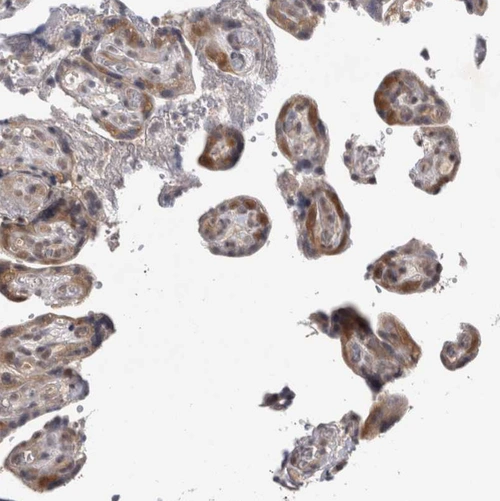

Immunohistochemical staining of human placenta shows moderate to strong nuclear and cytoplasmic positivity in trophoblastic cells.